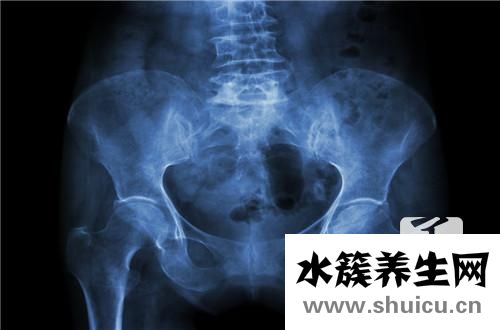

患有骨盆前傾,患者會出現便秘、月經不調等不良反應。及時糾正的最好方法就是加強鍛煉。仰面抬起骨盆,仰臥屈膝,以腳和背部為支點抬起骨盆,然后慢慢放下,重復20次。該動作可以是矯正 down 骨盆前傾。

1、仰臥抬起骨盆,仰臥位雙膝屈曲,以足和背部作支點,抬起骨盆,然后慢慢落下,反復20次,該動作能矯正下骨盆前傾。